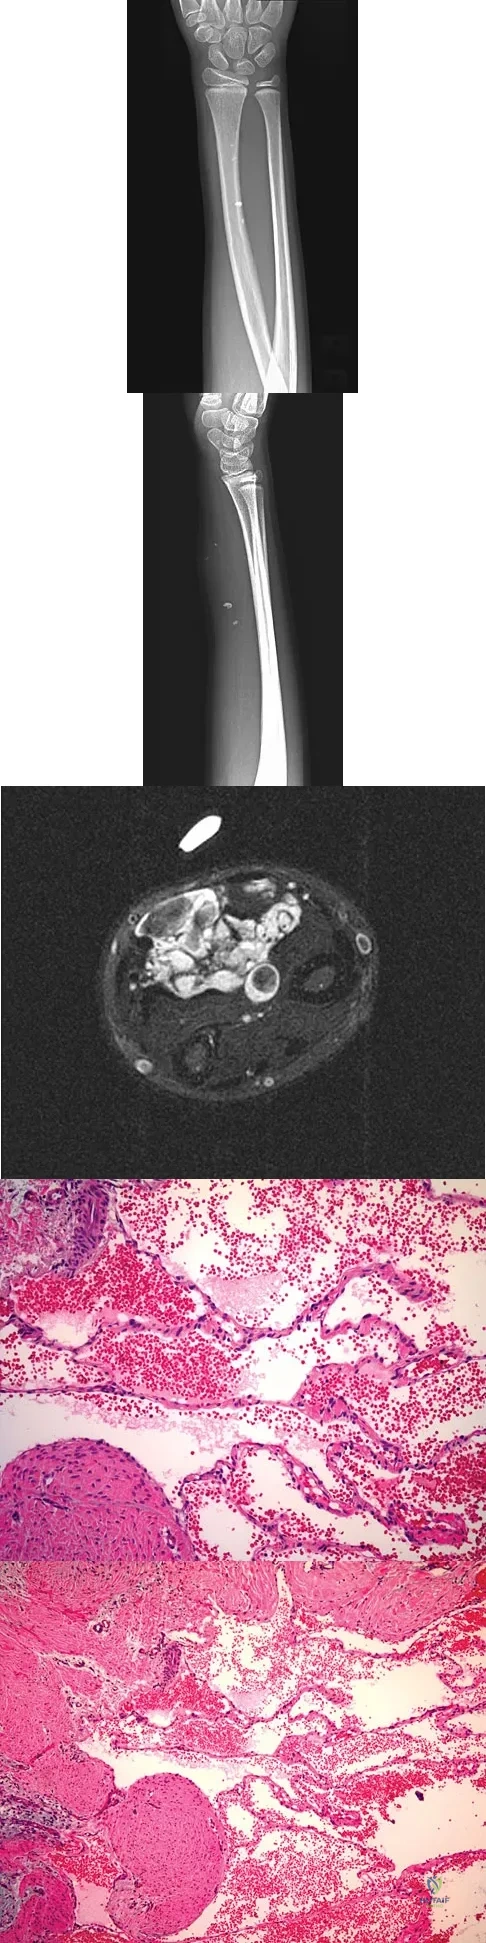

A 7-year-old girl has had a painful forearm for the past 2 months. Examination reveals fullness on the volar aspect of the forearm. Radiographs and an MRI scan are shown in Figures 42a through 42c. Biopsy specimens are shown in Figures 42d and 42e. What is the most likely diagnosis?

Explanation